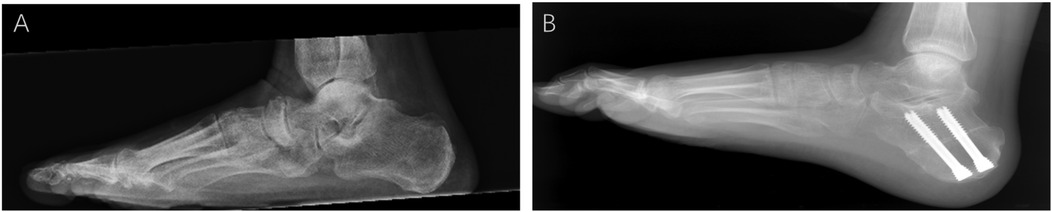

Patients were followed at 4 weeks, 3, 6, 12, and 24 months postoperatively. Pre- and postoperative AP and lateral weight-bearing foot radiographs, as well as hindfoot alignment views, were reviewed. Several parameters were measured by two independent observers, including the anteroposterior talocancaneal angle (kite angle), anteroposterior talus-first metatarsal angle (TM1), talonavicular coverage angle (TNCA), Saltzman’s view hindfoot moment arm (HMA), and the lateral talus-first metatarsal angle (Meary angle) (Figure 3) (7). For each parameter, the change was calculated as the difference between the pre- and postoperative values. The two investigators received training on unified measurement standards. At the final follow-up, ROM (plantar flexion and dorsiflexion) was measured by a goniometer. The Foot Functional Index (FFI) (8), the American Orthopaedic Foot and Ankle Society (AOFAS) Hindfoot Score, and the Foot and Ankle Ability Measure-Sports Subscale (FAAM-SS) were also assessed. Interevaluator consistency was verified using the intraclass correlation coefficient (ICC), with ICC values >0.85 for all indicators. For each patient, the final value was the average of the measurements taken by the two investigators to further minimize random error.

X-ray images of a foot and ankle with labeled angles. (a) Lateral view of the foot showing angles A, B, and C. (b) Top view of the foot with angles D, E, F, and G. (c) Rear view of the ankle displaying angles H and I. Lines are drawn to indicate different angular measurements for anatomical analysis.

Figure 3. Diagram of various angles in adults with acquired flatfoot deformity. (A) Lateral view: anteroposterior talocalcaneal angle (kite angle)—the angle between the central axes of the calcaneus and talus (A, B); lateral talus-first metatarsal angle (Meary angle)—the angle between the central axis of the talus and the central axis of the first metatarsal (A–C). (B) Anteroposterior view: anteroposterior talus-first metatarsal angle (TM1)—the angle between the central axis of the first metatarsal and the central axis of the talus (D, E); talonavicular coverage angle (TNCA)—the angle formed by the central axis of the talus and the edge line of the navicular joint surface (F, G). (C) Hindfoot coronal alignment views: Saltzman's view hindfoot moment arm (HMA)—the distance between the two points (H, I) is HMA.